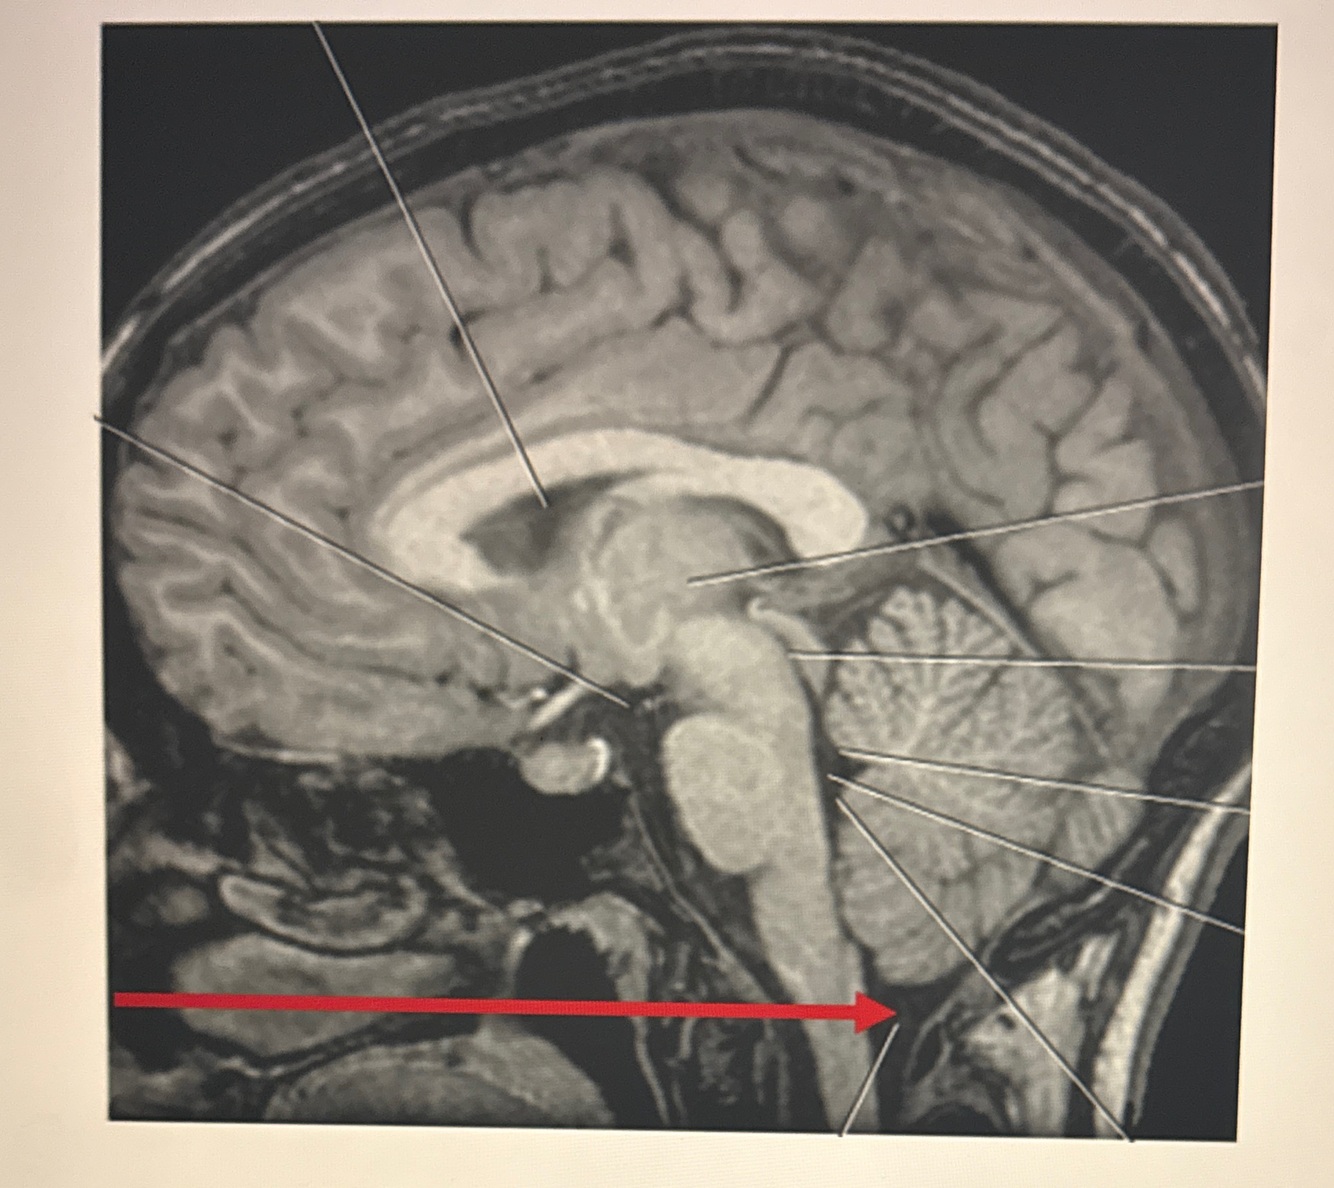

Q

Identify B

A. Thalamus

B. Mammillary bodies

C. Hypothalamus

D. Pituitary gland

A